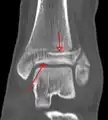

Sur les radiographies, on peut voir une fracture de la malléole médiale, de la malléole latérale et/ou du bord antéro-postérieur du tibia distal. Le bord postérieur (appelé malléole postérieure) est beaucoup plus fréquemment lésé que la face antérieure du tibia distal. Si les malléoles latérale et médiale sont brisées, on parle de fracture bimalléolaire (certaines d'entre elles sont appelées fractures de Pott (en)). Si la malléole postérieure est également fracturée, on parle de fracture trimalléolaire.[réf. nécessaire]

Vue AP en contrainte manuelle montrant une déchirure du ligament deltoïde.